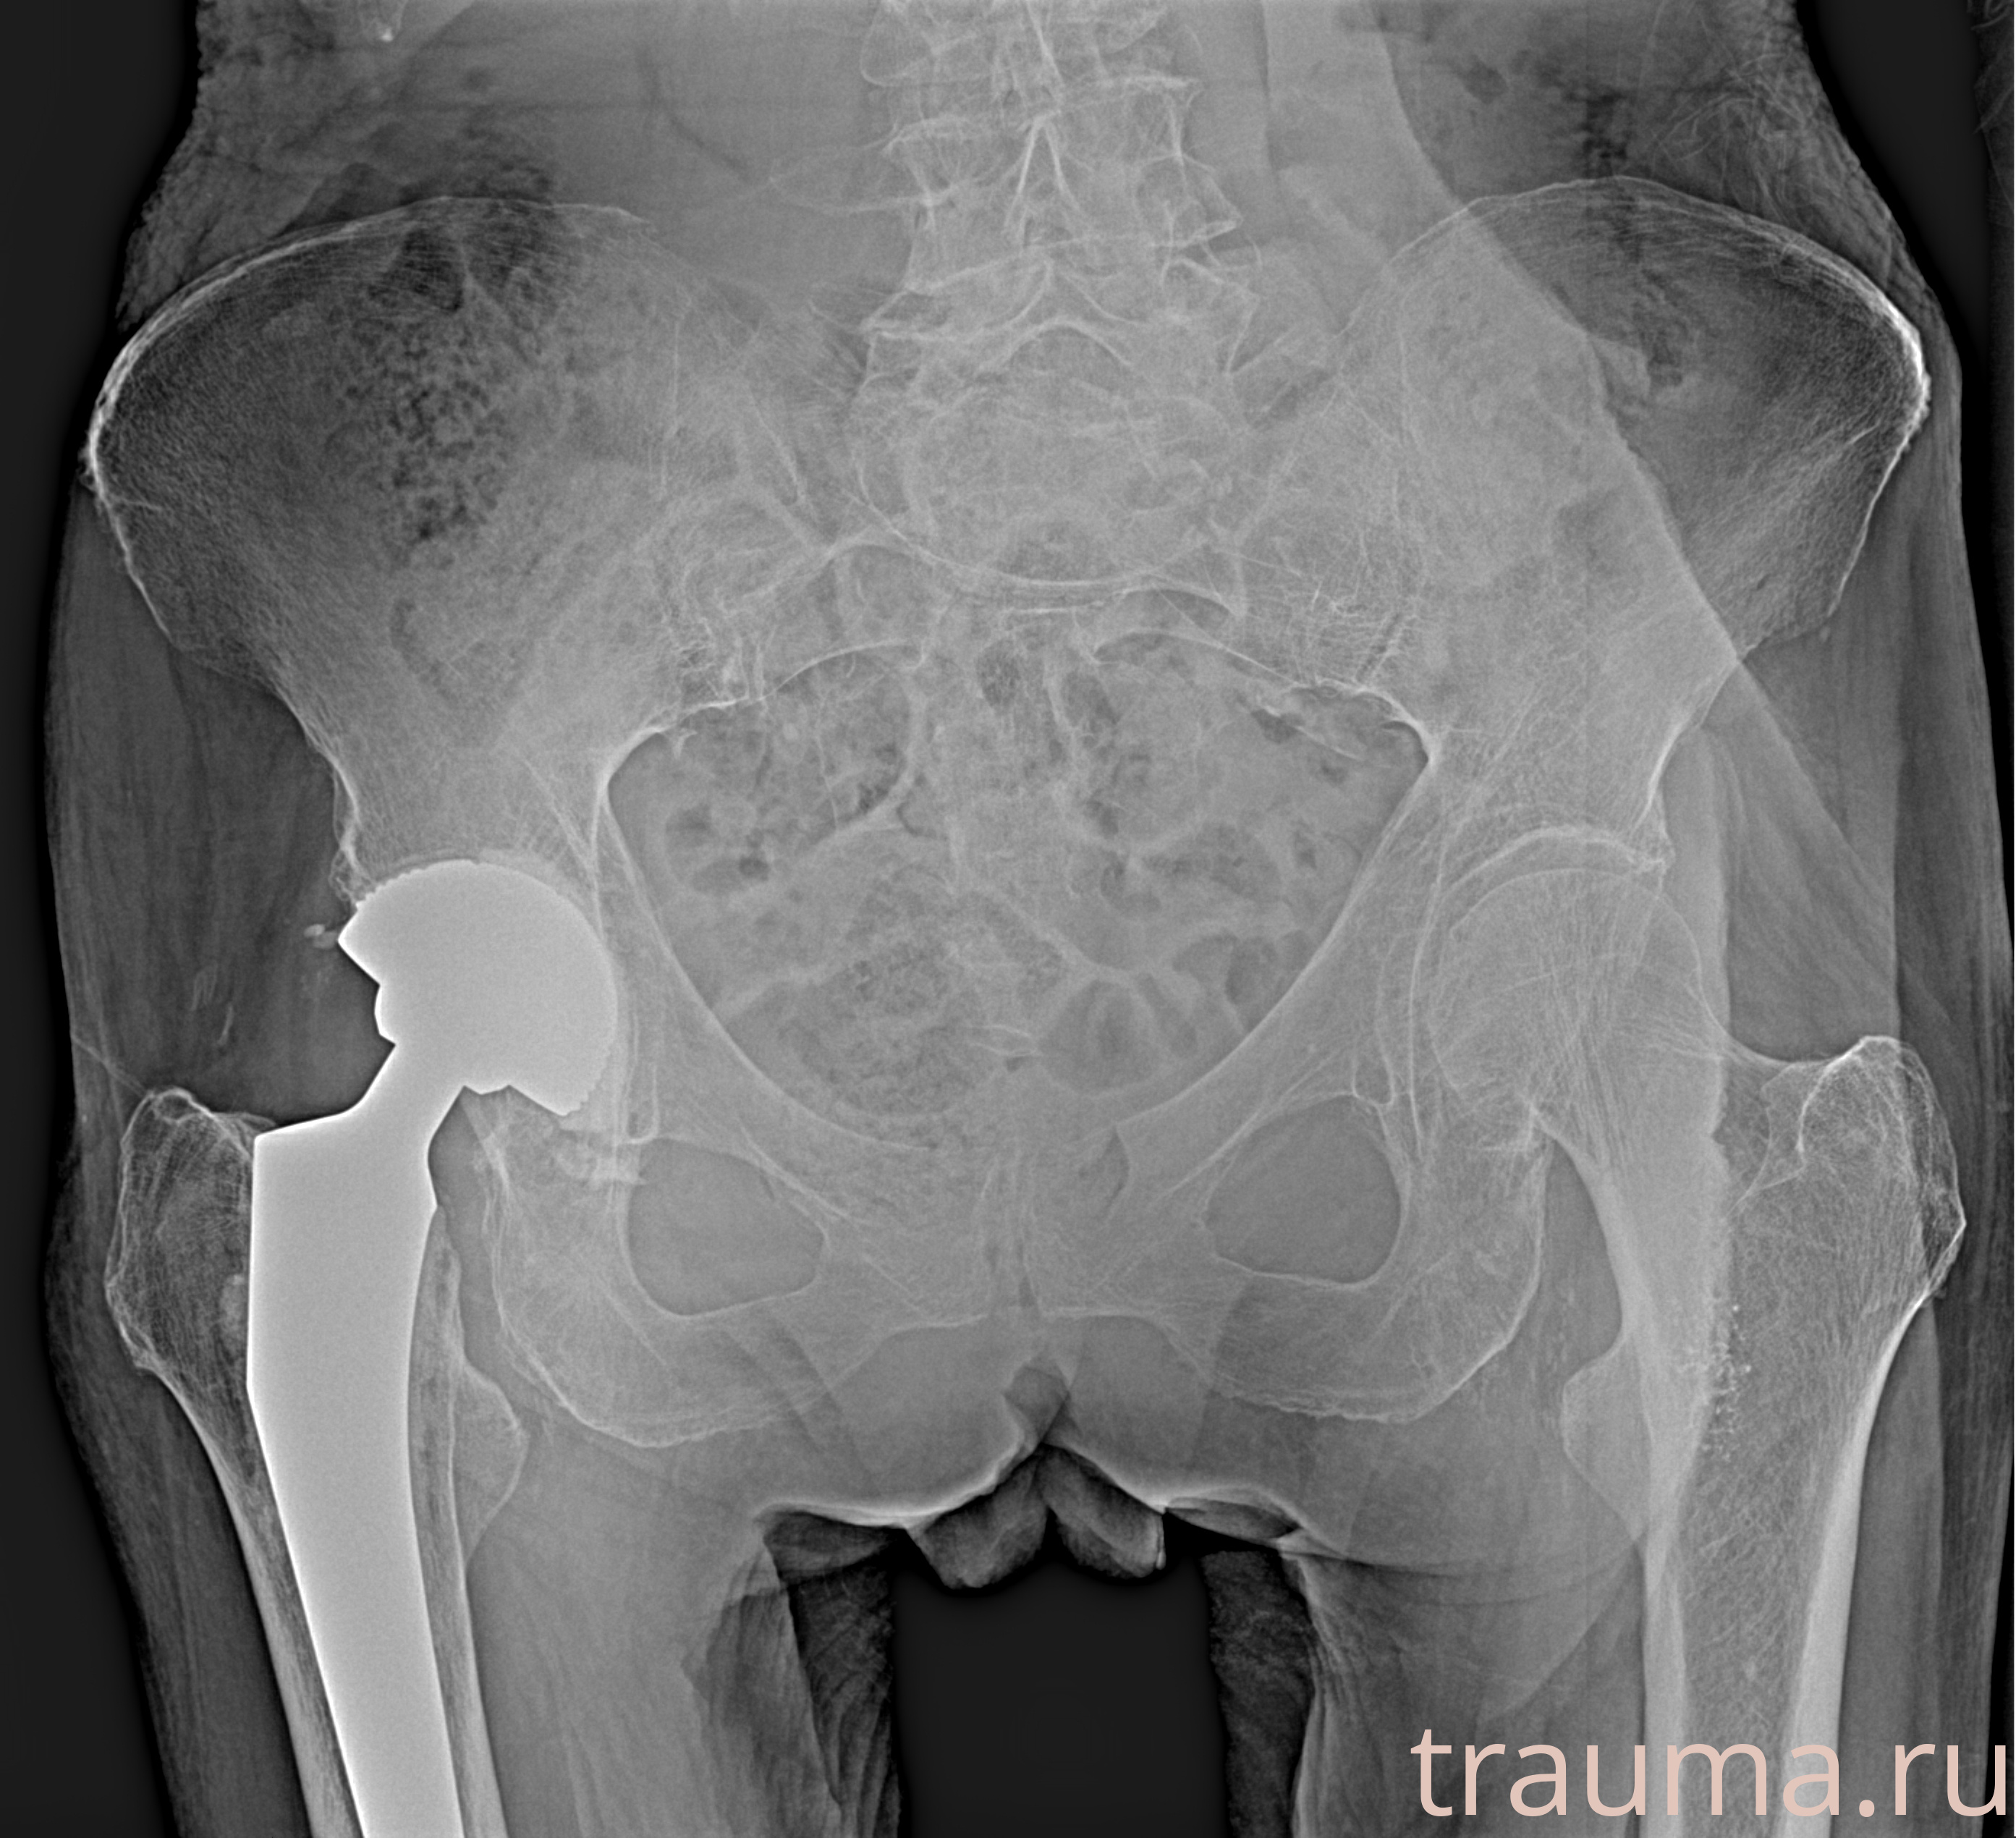

Рентген на дому: по вашему адресу приезжает врач-рентгенолог, травматолог-ортопед с мобильным рентгеновским аппаратом, проводит диагностику травмы или заболевания, делает необходимые рентгенограммы, дает рекомендации по дальнейшему лечению. Получить качественные снимки в домашних условиях возможно благодаря уникальной методике, разработанной МосРентген Центром для института  Склифосовского